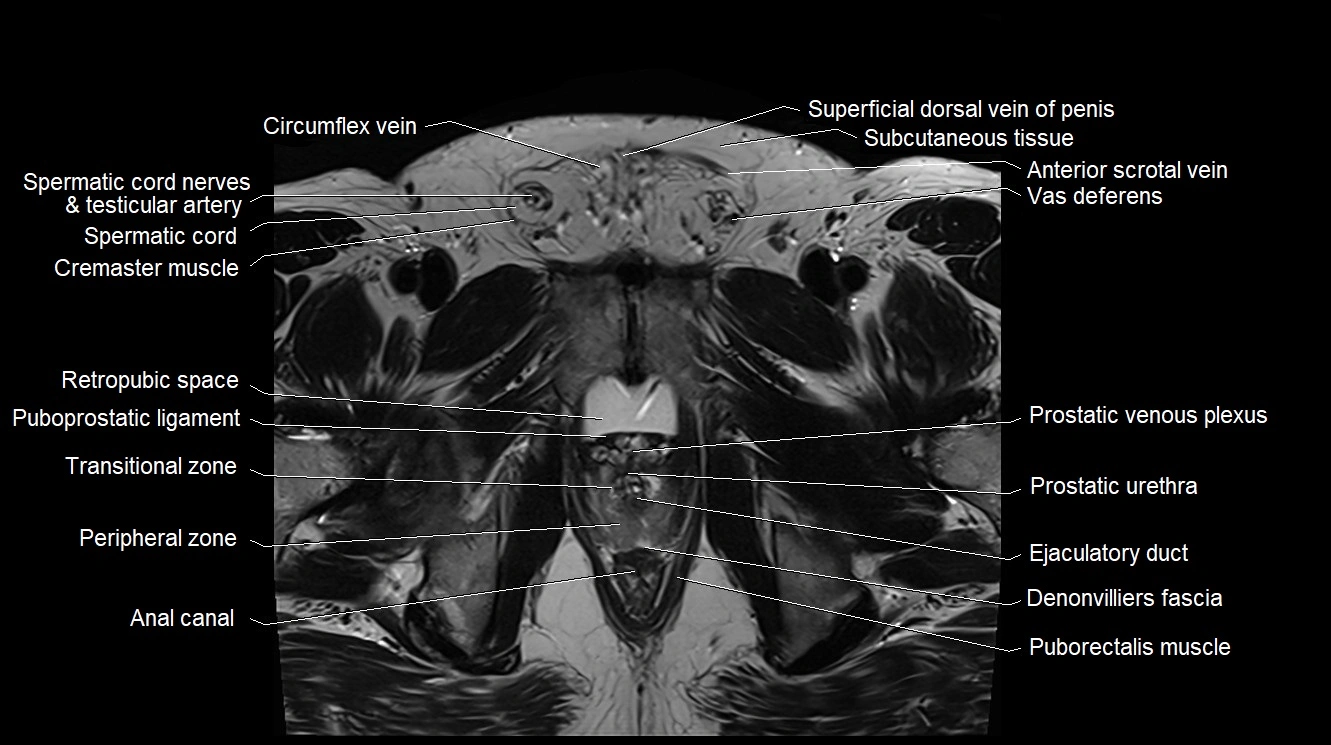

MRI image